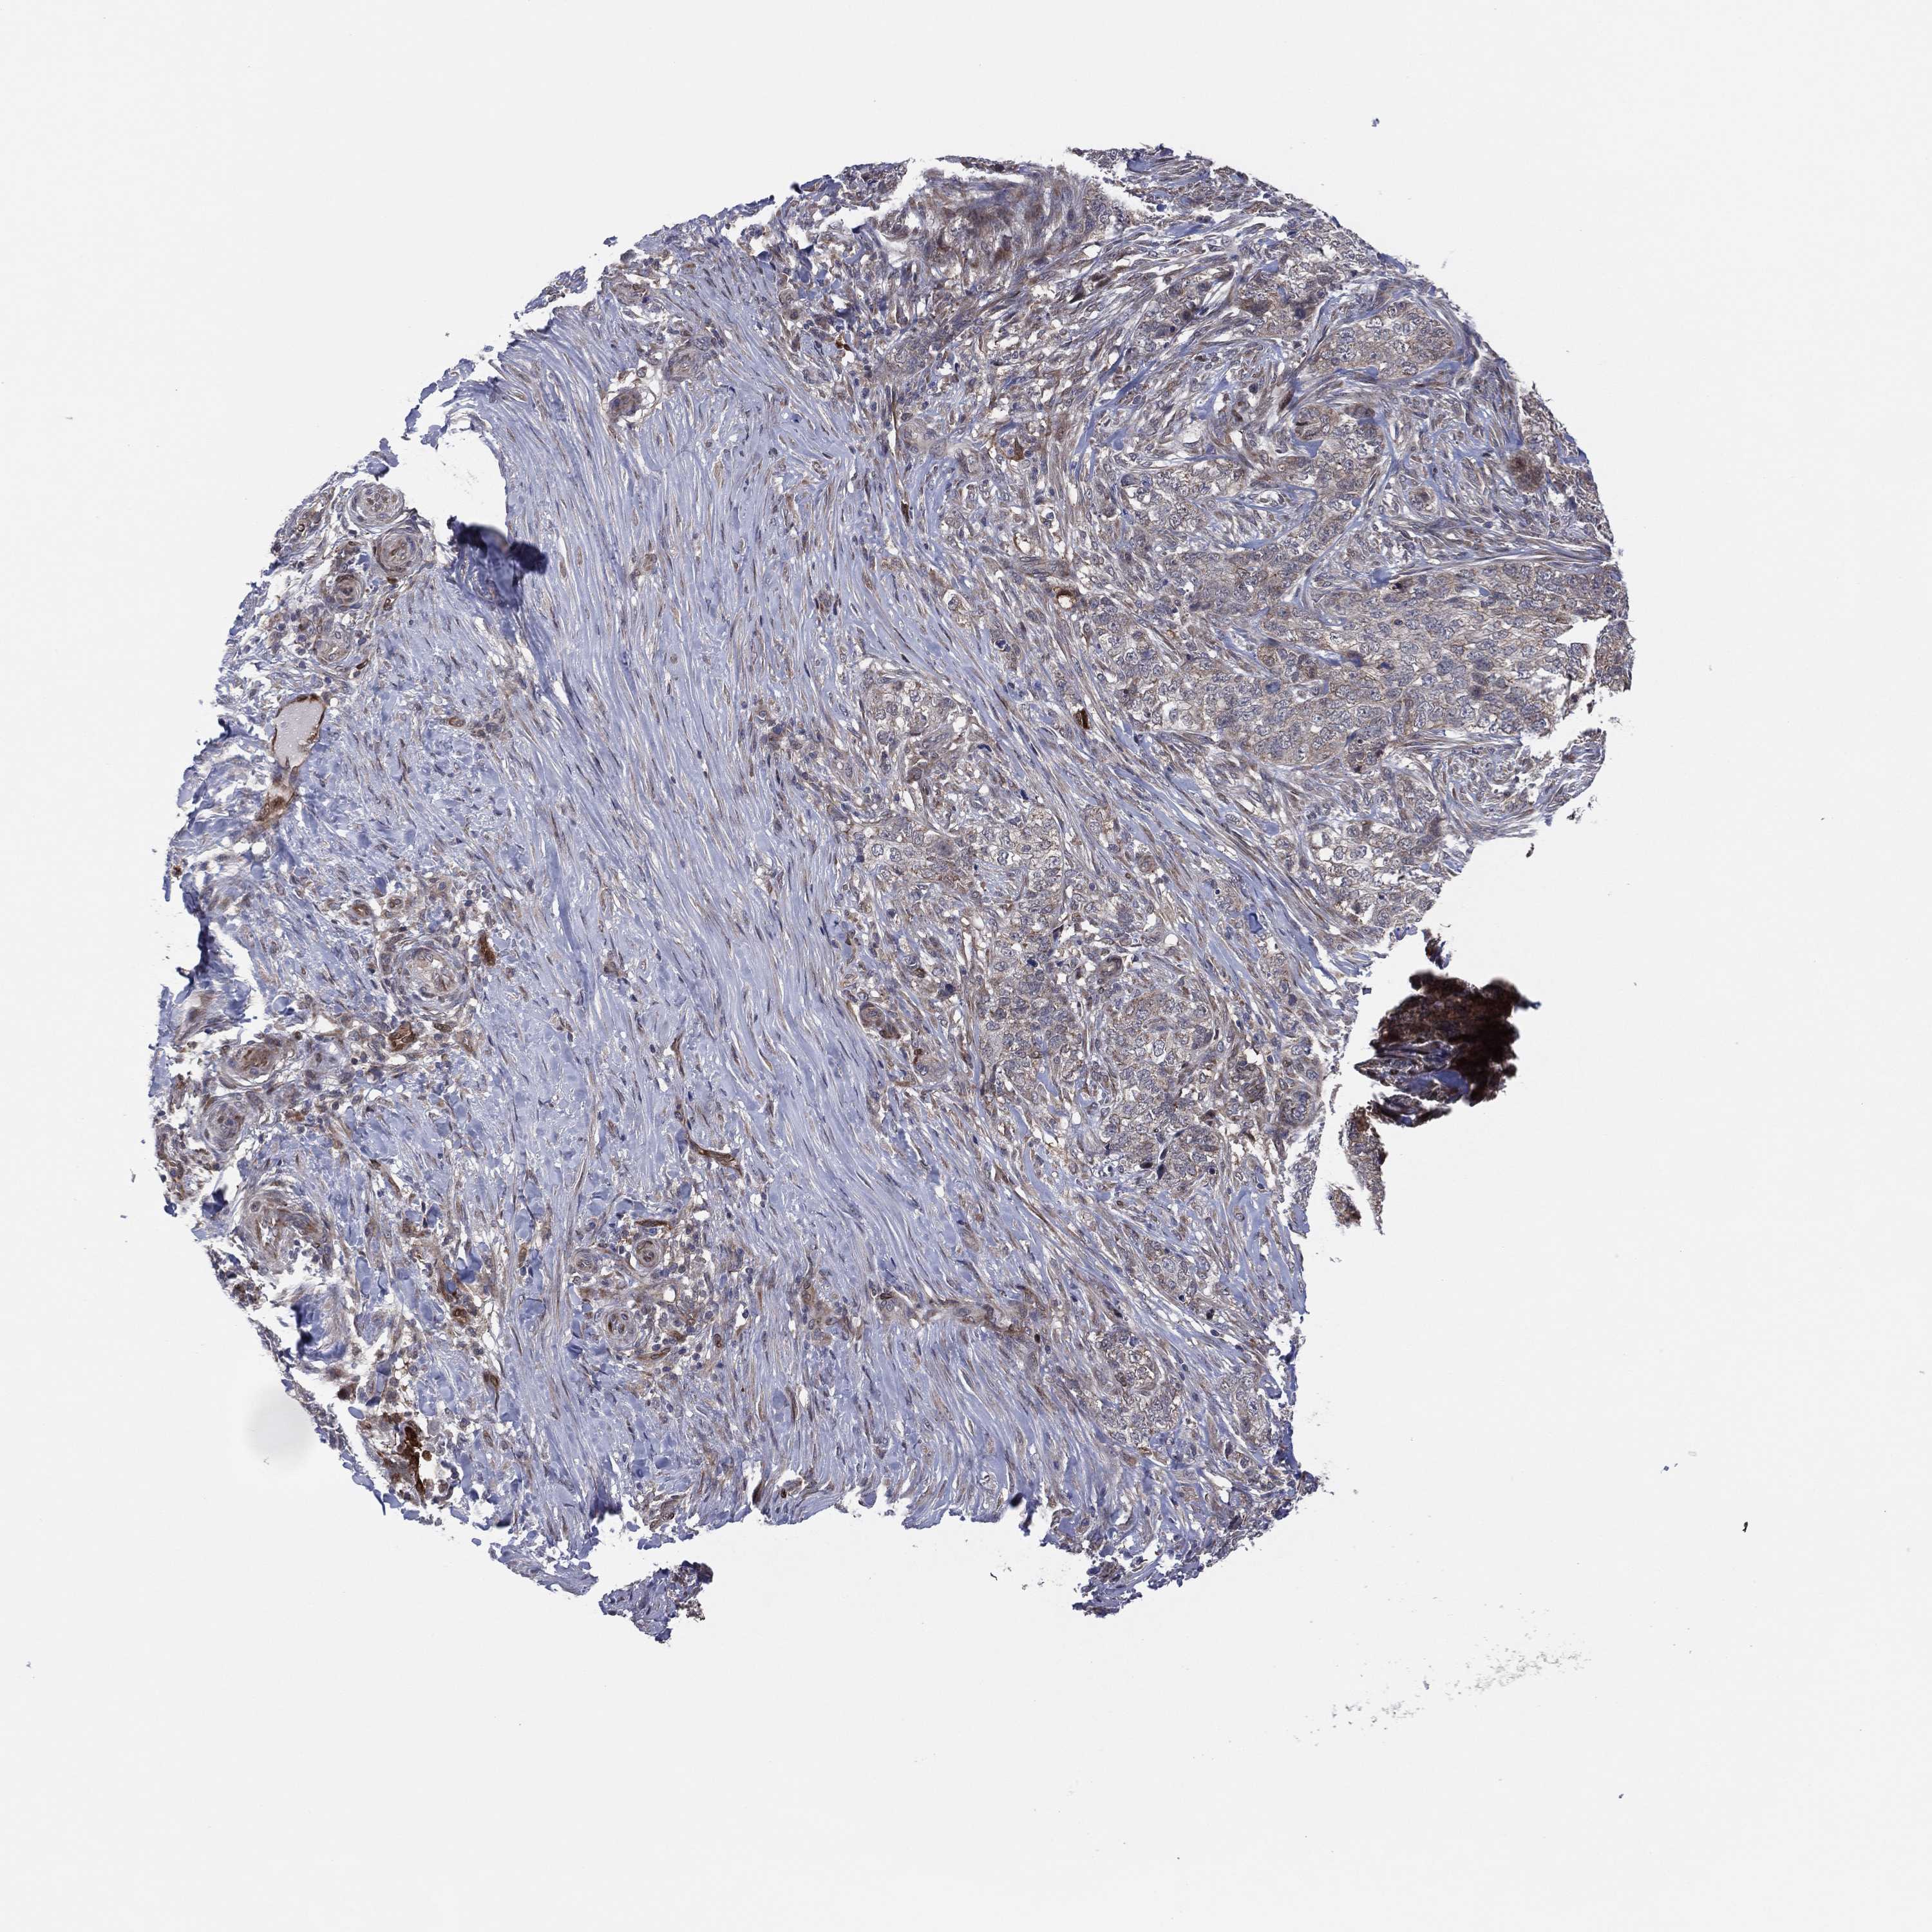

SKIN CANCER - Protein expressioni

A mouse-over function shows sample information and annotation data. Click on an image to view it in a full screen mode. Samples can be filtered based on level of antibody staining by selecting one or several of the following categories: high, medium, low and not detected. The assay and annotation is described here.

Each image is clickable and will lead to virtual microscopy that enables deeper exploration of all samples and also displays staining intensity scores, fraction scores and subcellular localization as well as patient and tissue information for each sample.

Antibody CAB080022

Squamous cell carcinoma, metastatic, NOS